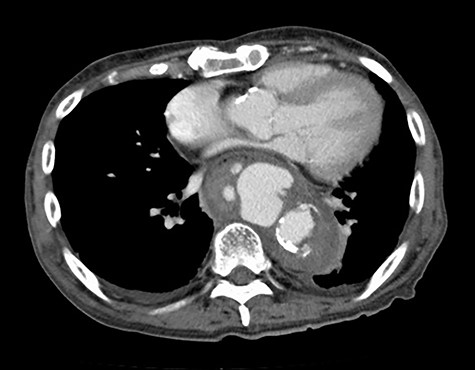

Seven days after TEVAR, the patient developed fever, and a CT scan showed bilateral iliopsoas abscesses and gas images inside the aneurysm (Fig. 2). We decided to perform upper gastrointestinal endoscopy and CT-guided drainage for abscesses. Endoscopy showed perforation of the esophageal wall and accumulation of necrotic tissue (Fig. 3).

CT seven days after TEVAR. Arrow shows gas images inside the aortic aneurysm.